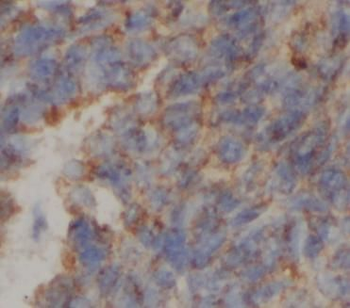

ATP5F1C Antibody

ATP5F1C

ELISA, IHC, WB

应用稀释比例:WB: 1:500-1:2000; IHC: 1:100-1:500